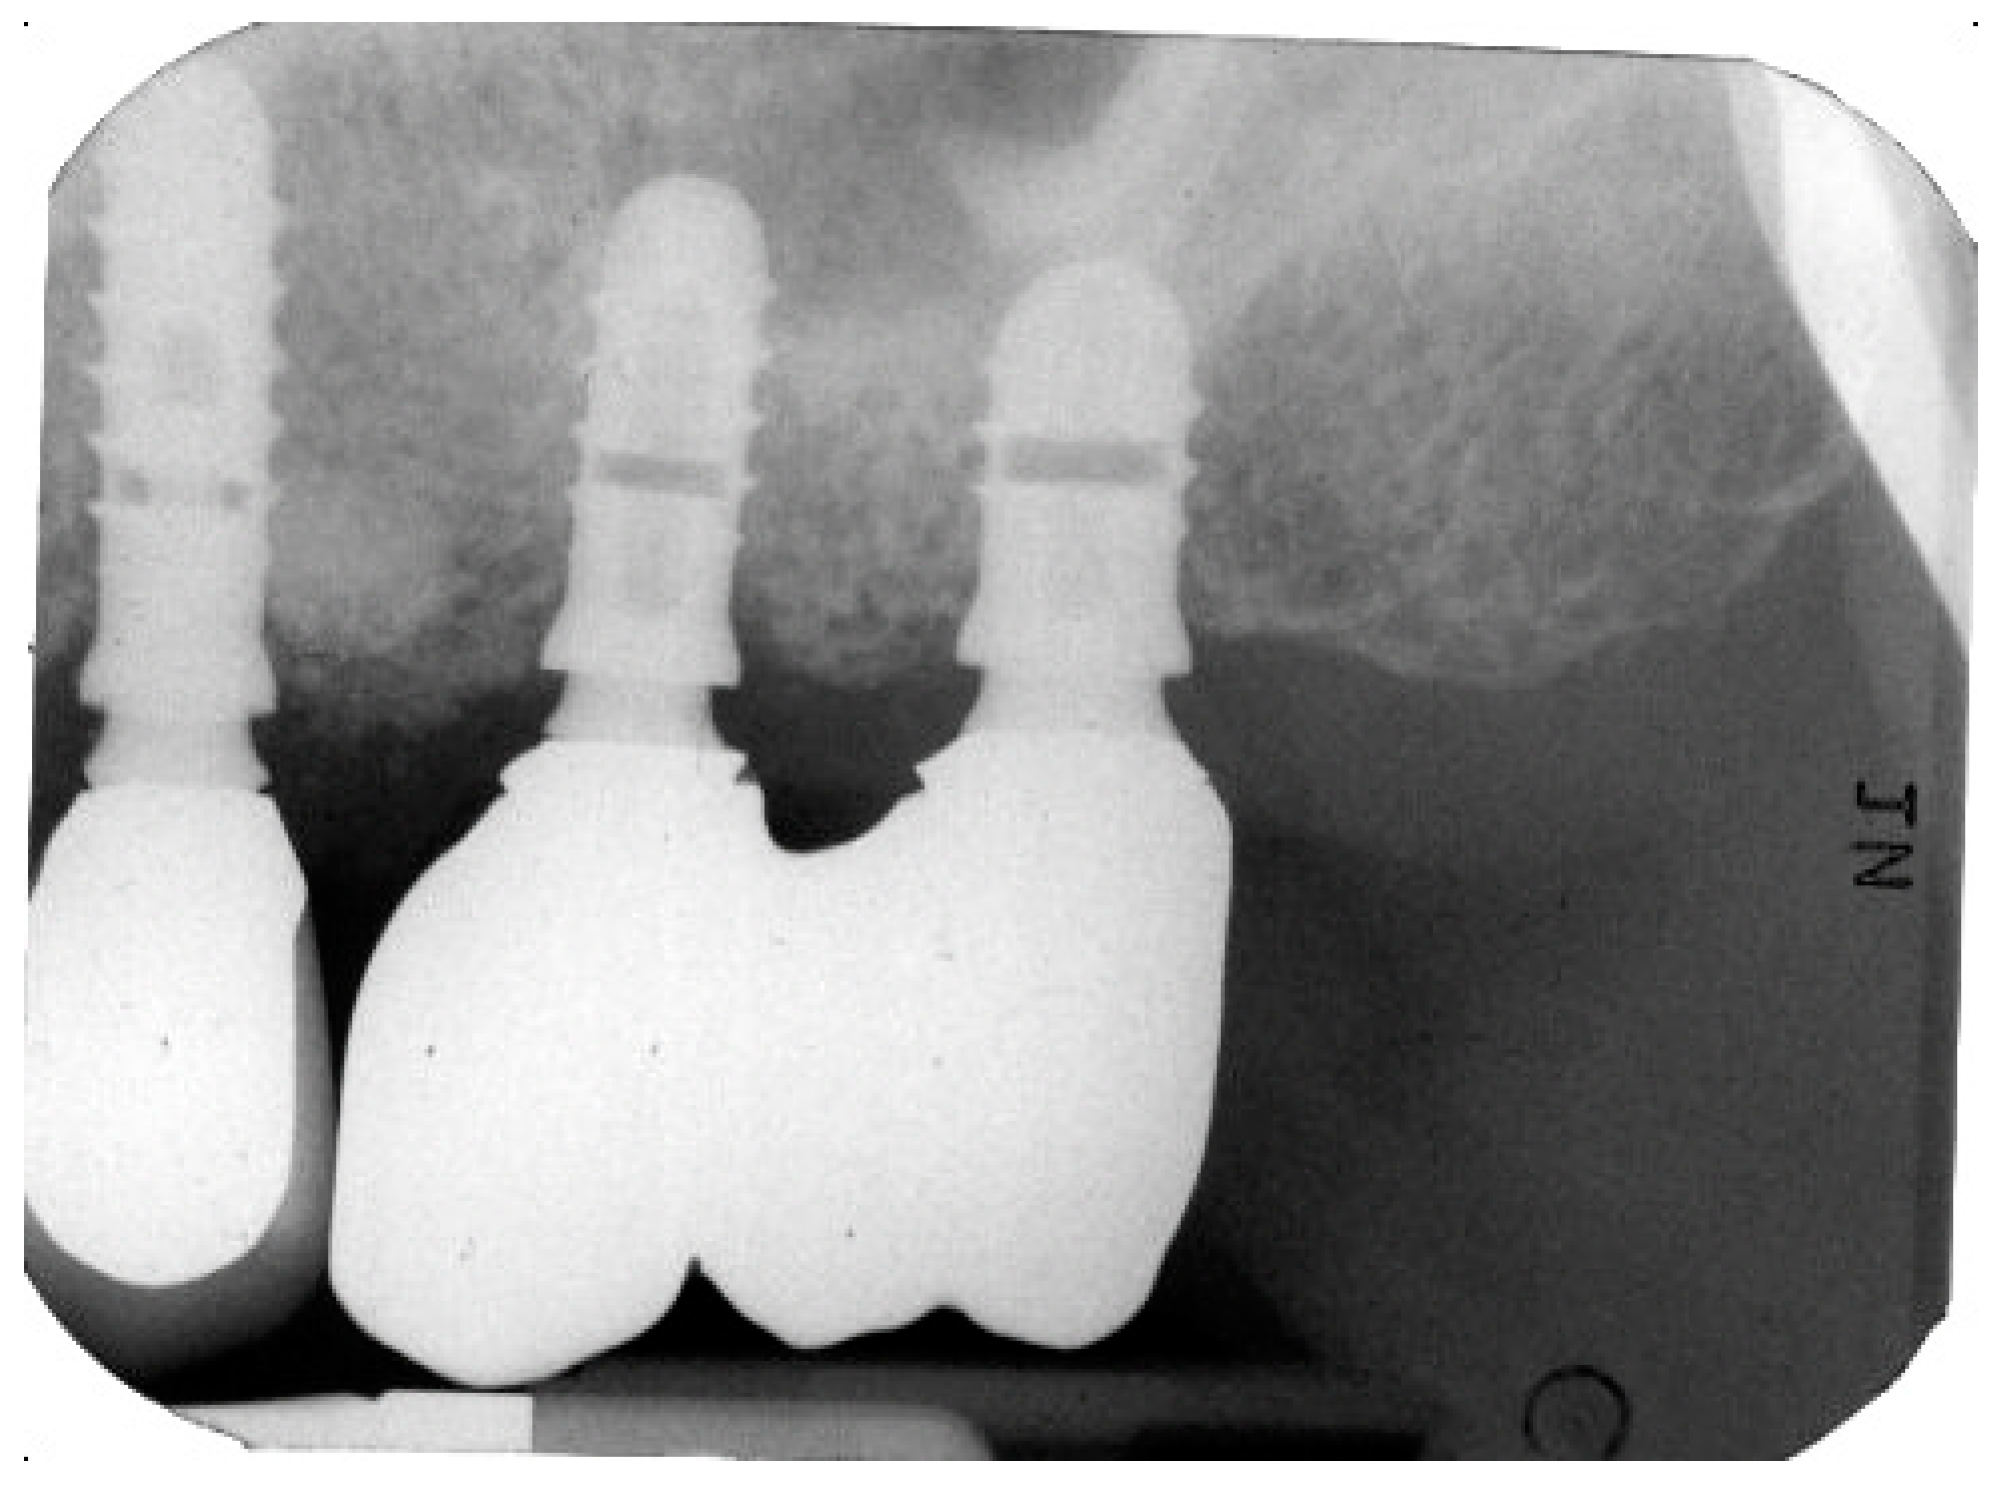

2.1. Implant Retrieval and Case Overview